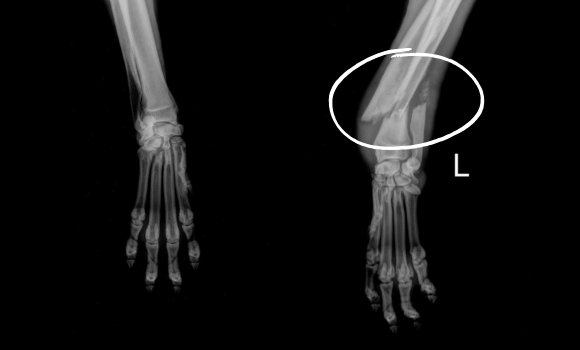

Petunia recently arrived at our Sam Swope Pet Treatment and Lifesaving Center unable to bear weight on her front left leg. X-rays revealed that this two-year-old pup’s radius and ulna are both severely fractured. We’re not sure what caused poor Petunia’s injuries, but we’ve promised her that we’ll get her started on the road to recovery as soon as possible.